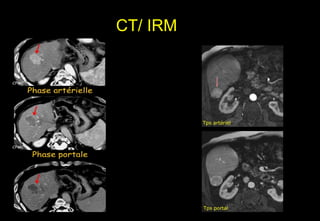

CT / IRM

• CĐ xác định:

- giàu mạch

- Wash out

- vỏ / mỡ / tăng tín hiệu T2 diffusion

CT/ IRM

Phát hiện CHC

• Kỹ thuật

– Ko cản quang T1 et T2

– Pha và đối pha+ diffusion

– Hình ảnh 2D hay 3D sau Gadolinum thì động

mạch, cửa và muộn

Quan trọng của thì tiêm thuốc